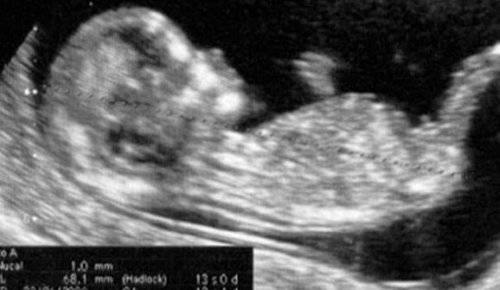

I den 13. uge af graviditeten kan ultralydet til slutningen af første trimester stadig udføres, hvis det ikke allerede er gjort.

Dette er det sidste skridt i serien af kontrolundersøgelser, som moderen skal have, da graviditeten først blev bekræftet.

Dette er det punkt, hvor evalueringen af første trimester afsluttes.